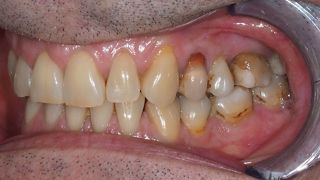

2a. 2b. Initial intraoral view of the molar.

2a

2b